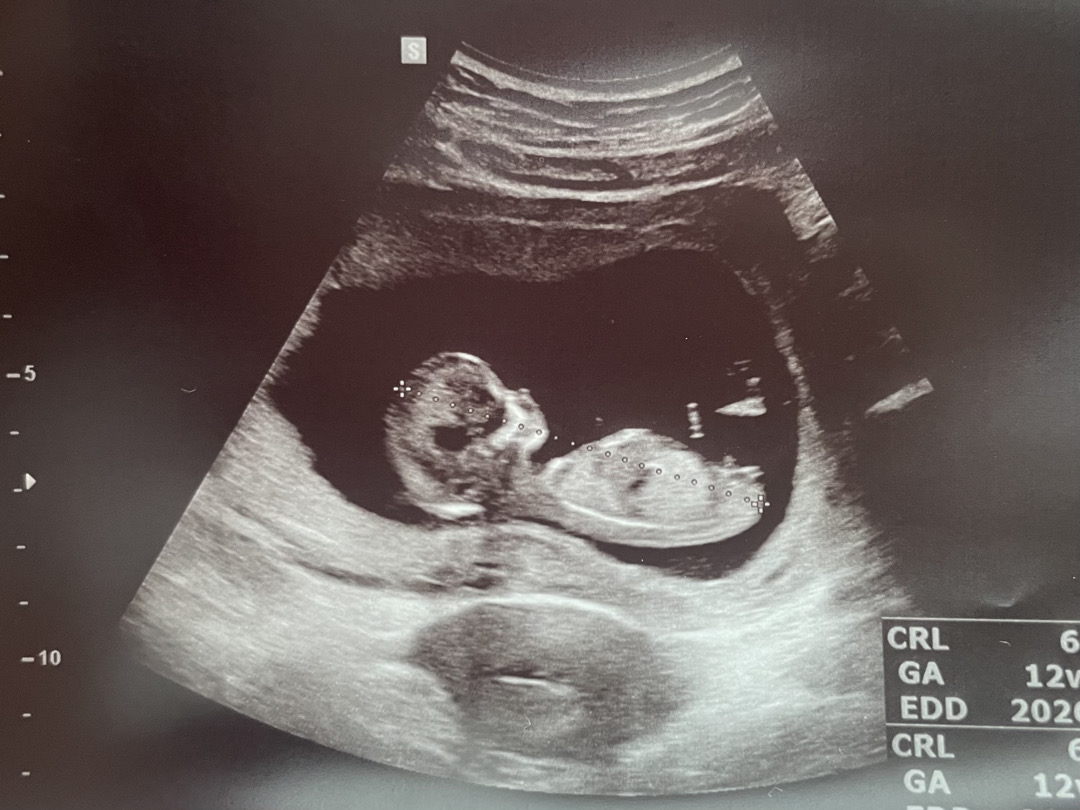

12주2일 각도법 궁금해요

각도법 많이 찾아봤는데도 어렵네요ㅠㅠ 아들일까요? 딸일까요?